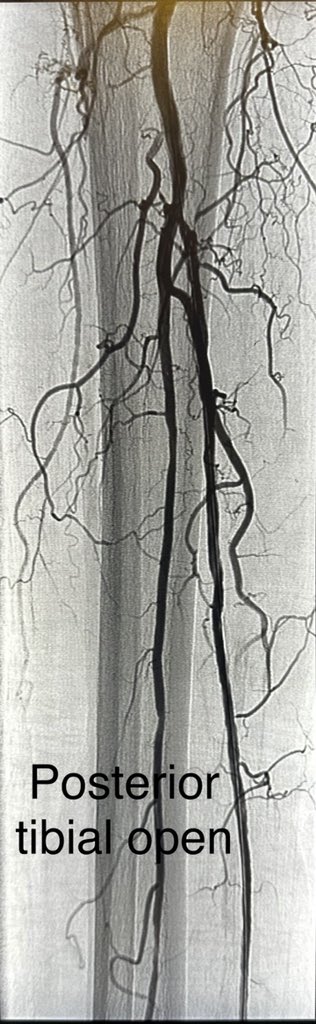

Patient in late 80s, non healing ulcers and ischemic pain in right leg. Complex multivessel tibial and pedal revascularization with #IVUS guidance, #Laseratherectomy and balloon angioplasty. Joys of limb salvage.@AMPSymposium @CLI_Global @Vascupedia_com

dr_ashishg's tweet image. Patient in late 80s, non healing ulcers and ischemic pain in right leg. Complex multivessel tibial and pedal revascularization with #IVUS guidance, #Laseratherectomy and balloon angioplasty. Joys of limb salvage.@AMPSymposium @CLI_Global @Vascupedia_com